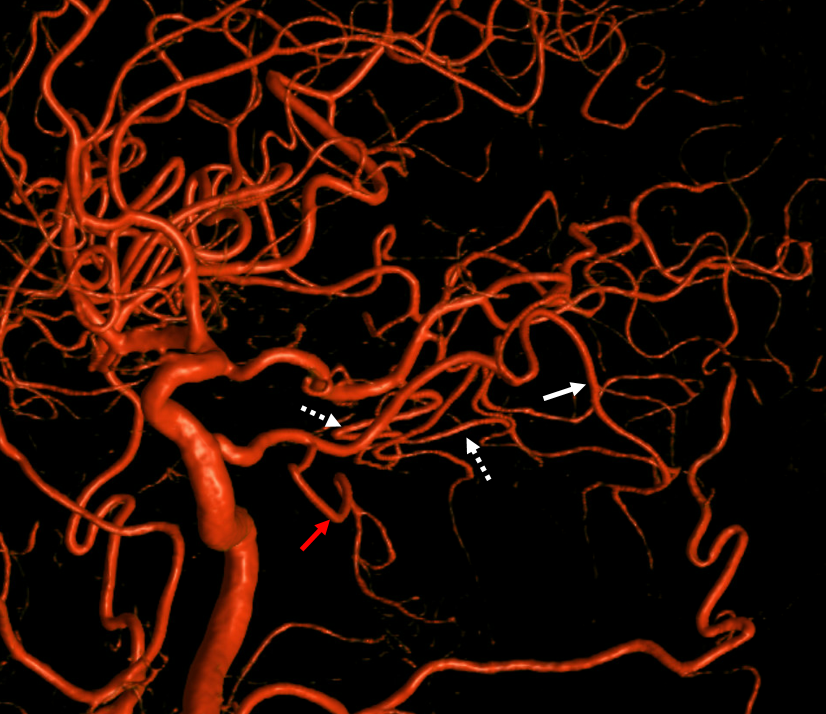

Trigeminal Supply of Superior Cerebellar, AICA, and lateral / hemispheric PICA

Neat. And extremely rare — i am not sure there is another example out there. I am very sure however that there are many people like that walking around, with no problems at all.

I guess that would be Saltzman IIIA+IIIB+IIIC/2. This is either very advanced algebra or a reflection on classifications in general — you decide. The important thing is to put everything together and understand what goes where

Angio shows large trigeminal with clear supply of the SCA on lateral view. Vert injection shows no right SCA. There is a diminuitive branch from mid-basilar projecting laterally — that is likely the right labyrinthine artery — what is embryologically solid AICA territory. The rest is taken by the trigeminal. The right PICA is limited to vermian territory. The inferolateral hemisphere is supplied by the trigeminal as well. Dont look for arrows. You should figure it out.

DYNA VR. White arrow — vermian branch SCA; dashed white arrows — lateral hemispheric branches of SCA; red arrow — AICA. Note inferior extension towards PICA territory.

MIP images. Superior vermian territory = white oval; lateral SCA territory = dashed white oval; AICA (minus the labyrinthine branch) = dashed black oval; inferior PICA/down to tonsillar branch = black oval